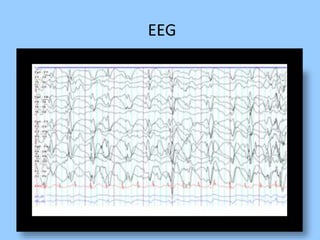

1. The document discusses EEG patterns and findings in various neurological conditions seen in children. It includes descriptions of normal EEG findings as well as abnormal patterns seen in conditions like absence seizures, West syndrome, benign childhood epilepsy with centrotemporal spikes, Lennox-Gastaut syndrome, non-convulsive status epilepticus, subacute sclerosing panencephalitis, and herpes encephalitis.

3. International standards for EEG electrode placement and recording parameters are reviewed. Characteristics of different EEG waves, amplitudes, and patterns are described.